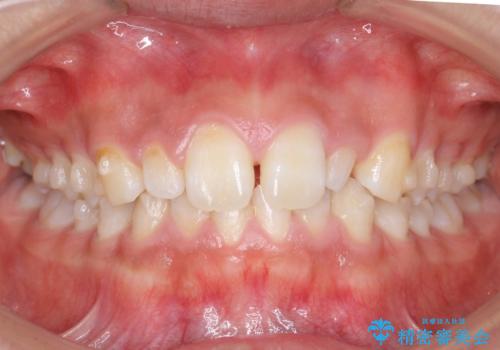

前歯のすきま 矯正治療とセラミックで小さな歯を形良く

- 前歯のすきまを気にして来院。

左上の2番が生まれつき小さく、スペースが余っていました。

右上の2番もやや小さめでしたが、相談の上、左上2番のみセラミックで形を整えることとしました。

そのほかの隙間はマウスピース矯正で閉じることにしました。